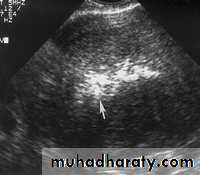

Endometritis. US image demonstrates multiple echogenic foci within the endometrium (arrow) representing gas.